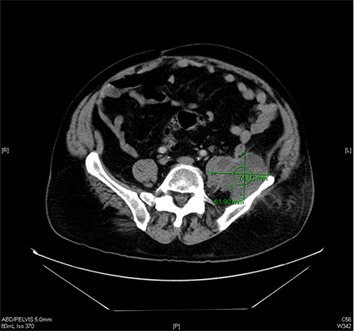

One week after the procedure, the patient developed left groin pain radiating to the left knee. The patient denied any fever, weight loss, night sweat, chills or rigors. A conservative management using NSAIDs was opted. The pain continued to worsen prompting an emergency room (ER) visit. On ER presentation, his vital signs were within normal limits. Physical examination was positive for pain on the left hip that was exacerbated by palpation. A 3 x 8 cm area of erythema and tenderness on the left flank was noted. The femoral vein area was thoroughly examined. The area was well healed without any sign of infection. Cardiovascular examination was negative for murmur. Laboratory examination revealed mild leukocytosis (WBC=14.5 K/uL). Other important pertinent laboratory tests include ESR (53 mm/hr), CRP (10.51 mg/dL), Creatinine (1.59 mg/dL), Lactate (1.3 mmol/L) and Creatine Kinase (46 U/L). Urinalysis was unremarkable. CT scan of the abdomen revealed an approximately 6 cm multiloculated fluid collection arising from the iliac involving the left psoas, iliacus, and quadratus lumborum muscles [Figure 1] and [2]. In addition, a curvilinear, soft tissue density mass in the central mesentery measuring 2.5 x 6.4 cm was also found. The vascular grafts from prior procedures were widely patent. CT guided abscess aspiration and drain placement were performed. Prior to the culture data, the patient was treated empirically with vancomycin and piperacillin/tazobactam. Microbiology examination revealed Eschericia coli and Prevotella loeschii. The flow cytometry did not reveal any malignancy. The patient was treated according to the culture and sensitivity data with ertapenem 1 gram daily from the time of drain removal for a total of two weeks. The patient remained stable and was discharged with a close follow-up. The patient was scheduled for biopsy of the suspicious mass in the central mesentery.

Figure 1. Transverse section of the CT shows multiloculated fluid collection arising from the left iliac fossa measuring ~ 6.2 x 7.5 cm involving the involving the left psoas, iliacus, and quadratus lumborum muscles.